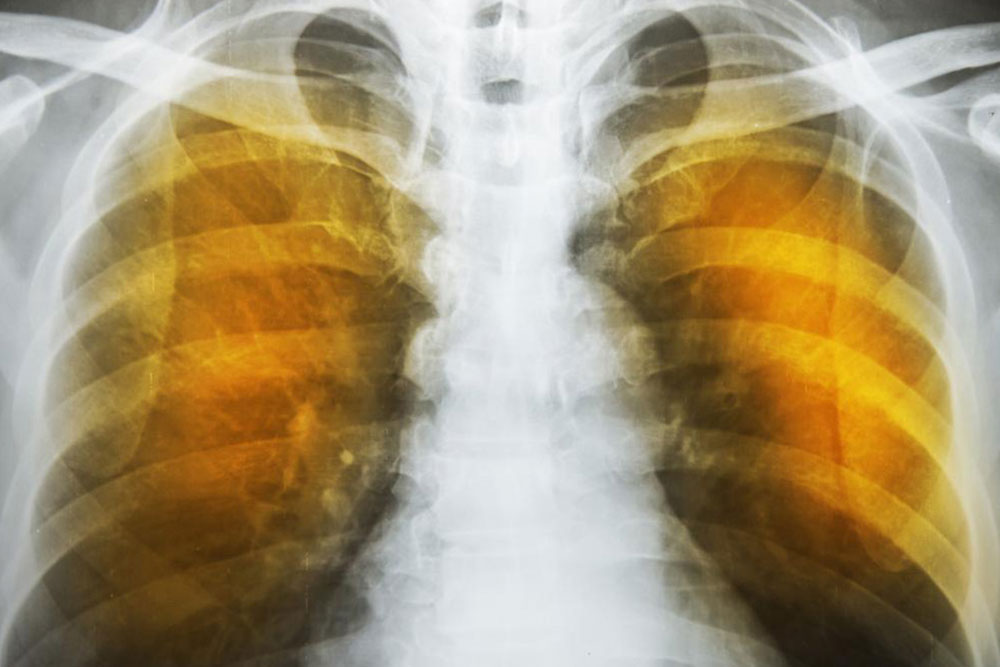

Emphysema symptoms: What you ought to know

Emphysema is caused by continuous exposure of the bronchioles to irritants such as cigarette smoke, passive smoke, industrial solvent fumes etc. This makes the muscles of the bronchioles contract. Chronic exposure to irritants make these muscles contract permanently. Then, the mucus membrane lining the bronchioles start secreting mucus in order to wash away particulate irritants. Both these body reactions are to restrict the entry of the irritants into the cavities of the bronchioles and alveoli.

The next reaction is to cough out the irritants and the mucus. Severe forceful coughs can raise the pressure in the alveoli considerably and can rupture their exceedingly thin walls.

The reduction of area for gas transfer and the loss of elastic tissues in the lungs reduces the capacity of the lungs to expel air. This reduces the intake volume of fresh air during breathing and can also lead to infections. These conditions produce the characteristic symptoms of wheezing, tightness in chest, labored breathing and coughing. These are also indications as well as symptoms of severe asthma.

The symptoms of emphysema are exceedingly severe and cause considerable damage to the lungs before the symptoms even show up. Generally, one feels a lack of energy and the tendency to skip some of the common daily routines.

It progresses from slight difficulty in breathing to wheezing and then to a persistent cough that does not go away. One starts to feel a tightness in the chest and feels short of breath on exertion. Tiredness and persistent cough become constant.

Infections can set in, turning the sputum yellow, which also leads to loss of appetite, further aggravating tiredness. One will lose sleep and even sexual function. All this constant suffering and ill health lead to depression which would in turn lead to the patient needing psychiatric help. The lips and fingernails turn blue or gray due to lack of oxygen in the blood. One may get into a condition called hypoxia and may have to resort to oxygen therapy.

As the deterioration continues, the alveoli lose their strength and start rupturing. In extreme cases, there may be large scale destruction which leads to empty spaces in lungs called bullae. This would reduce the functional area of the lung which in extreme cases call for surgical removal. In an extremely rare condition, large scale rupture of alveoli can cause a condition called pneumothorax and the collapse of the lung, a very serious condition, which can be fatal. The best thing one can do is stop exposure to irritants.